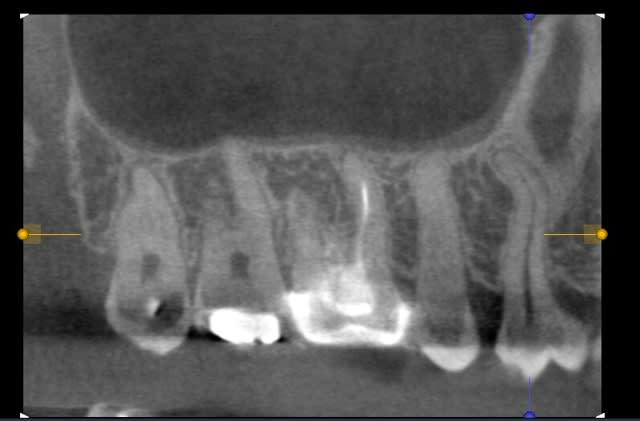

çà y est le cone-beam 3D I-Cat est installé depuis jeudi avec un PC plein de mémoire et une carte graphique du diable. J'ai déjà réalisé 3 examens. Le positionnement du patient est simple, l'environnement logiciel assez intuitif.

Faudrait que je vous fasse quelques copies d'écran mais dores et déjà je trouve que les clichés sont vraiment de bonne qualité. Quel confort! les mesures se font au quart de poil.

les premières copies d'écran (je ne maîtrise pas encore le logiciel)